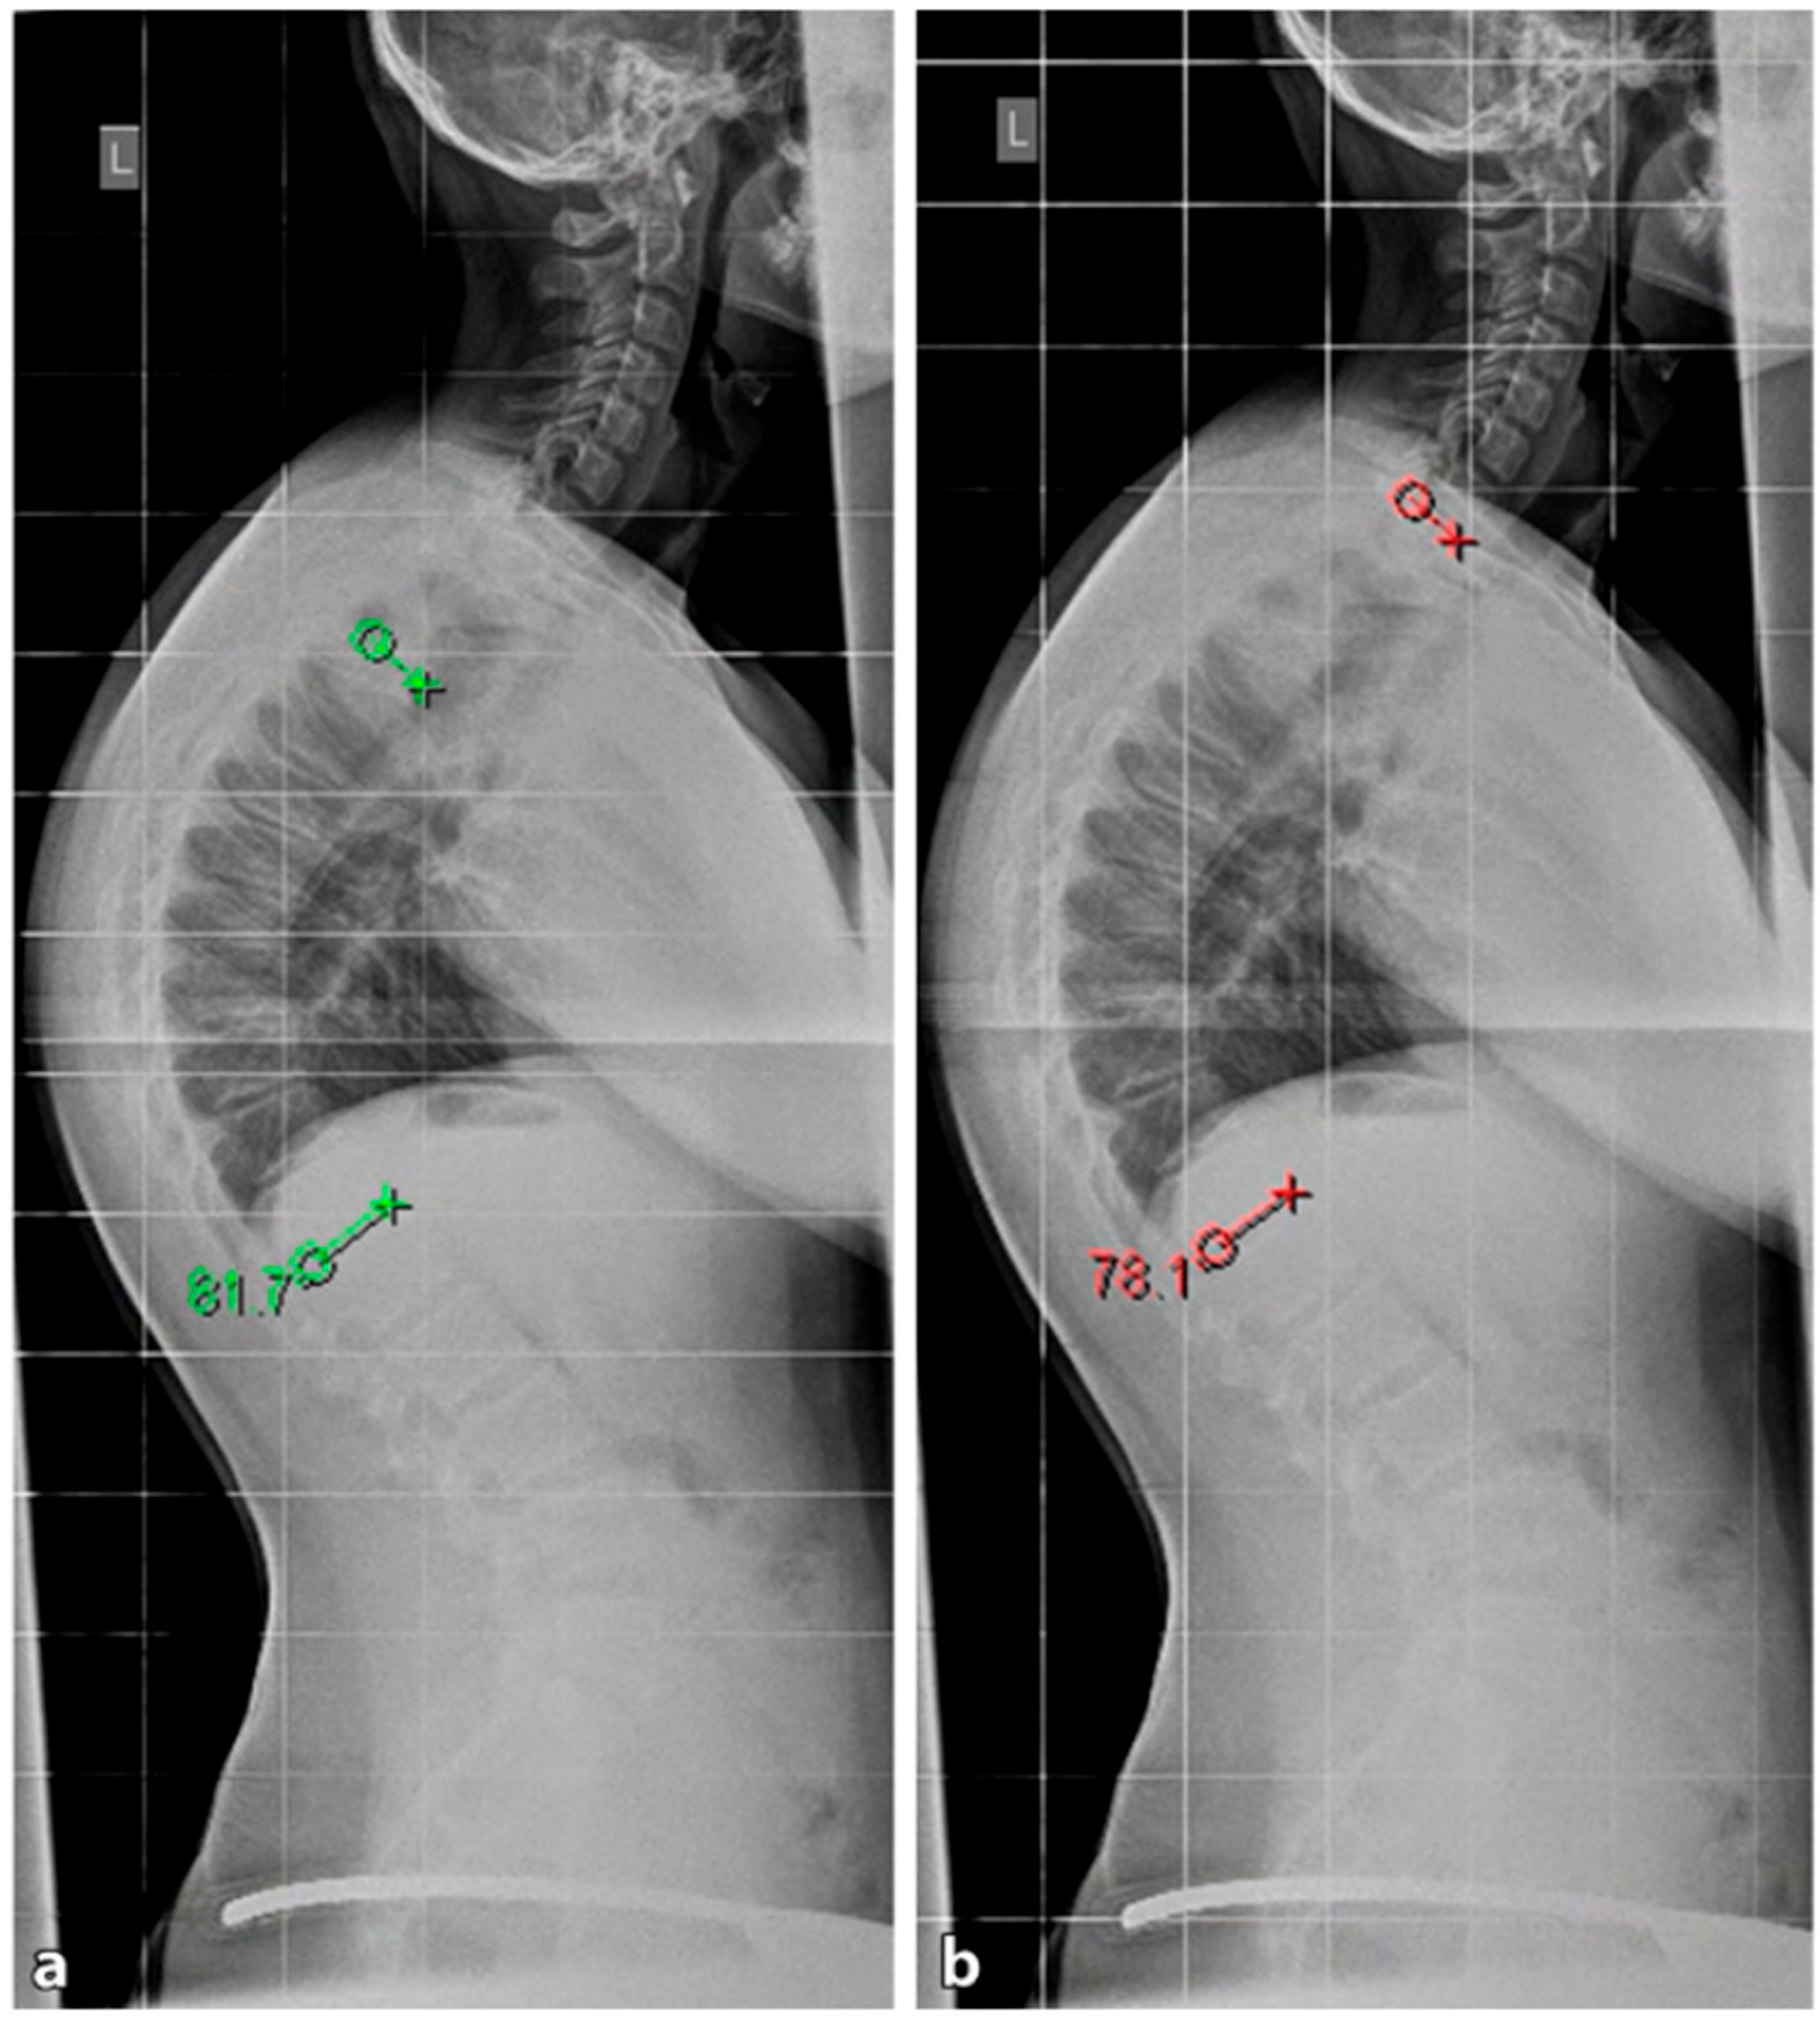

4.2. Diagnostics

Although initially described by Sorensen, the definition of SD has been definitively established by subsequent work by Edgren et al. and Blumenthal et al., with SD typically manifesting mostly in the thoracic spine (type I) and less commonly in the lumbar spine (type II) [79,85,86]; see Figure 7. The measurement of thoracic kyphosis according to Cobb (Th1–Th12) is sometimes difficult on conventional X-rays due to the humeral heads, so the Stagnara angle (Th4–Th12) is a reliable alternative (Figure 8). In children with SD, back pain and a positive family history are common, and clinical examination typically reveals a gibbus and a flexible deformity. In addition to a detailed medical history, a thorough physical examination is of utmost importance. The various signs and findings typical of SD are listed in Table 2.

4.2.1. X-ray

A standing anterior–posterior and lateral spinal radiograph is part of the standard imaging. Stereoradiographic imaging can be used alternatively to conventional radiography to create a three-dimensional reconstruction of a biplanar spinal X-ray with significantly less radiation exposure (EOS™) [31]. In addition to the representation of the kyphosis in the lateral view, these images also show the extent of curvature in the frontal plane according to Cobb, the curvature pattern, the sagittal profile or sagittal balance, and the apical vertebra. An assessment of spinal flexibility can be made using a clinical examination or a hyperextension lateral radiograph. The various features can be observed in radiological diagnostics, as shown in Figure 7. In up to 50% of cases, scoliosis and spondylolysis are accompanying pathologies [87,88].